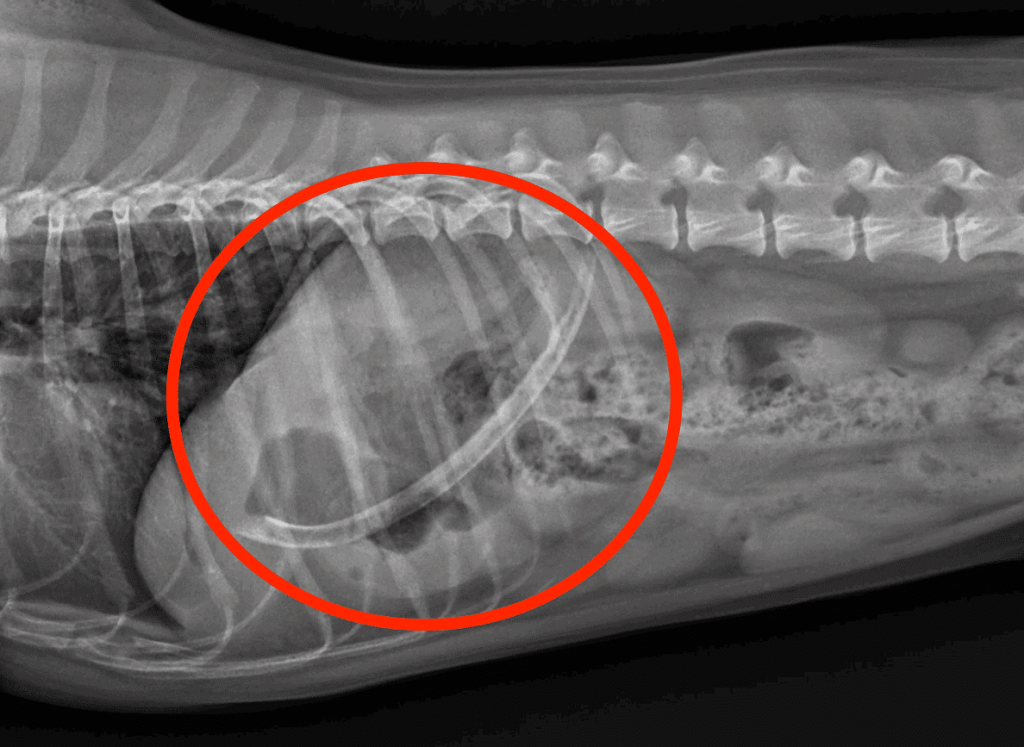

While everyone, pets included, enjoys a barbeque, a dog’s indiscriminate eating habits make barbeques hazardous. Take for example the wooden skewers used to grill meats and vegetables. When ingested by a dog, they don’t show up on x-rays because they’re wooden, and they wreak havoc when they pierce the intestines. Even barbeque clean up poses a risk—the x-ray accompanying this blogpost above shows a dog that ate a metal scrubby used to clean a grill. It was covered in food grease and smelled delicious to a canine nose. Sometimes it’s the humans doing the grilling that are the problem when they “give a dog a bone.” AMC’s ER veterinarians remove bones stuck in the throat all too commonly. See examples below.